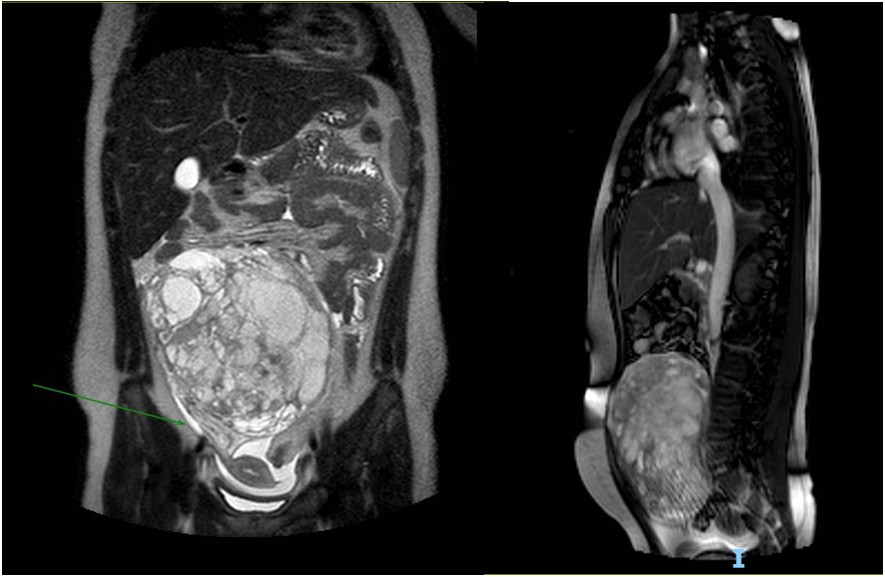

Se solicita RM de pelvis con contraste que evidencia formación tumoral abdomino-pelviana central en íntimo contacto con el peritoneo sin claro plano de clivaje con el mismo. La misma presenta bordes bien definidos de intensidad heterogénea multiquística con tabiques y realce heterogéneo con contraste. Se identifican áreas de restricción en difusión. Mide: 14.4 x 7.4 x 14,2 cm (ver imagen 2). La imagen impresiona en relación al anexo derecho. Se evidencia dilatación urétero-pielocalicial derecho.

Imagen 2. Resonancia magnética. Cortes coronal y sagital en t2. Se identifica formación tumoral abdominopelviana central en íntimo contacto con el peritoneo sin claro plano de clivaje con el mismo. La misma es ovoidea de bordes bien definidos de intensidad heterogénea multiquística con tabiques y realce heterogéneo con contraste. Mide: 14.4 x 7.4 x 14,2 cm que podría corresponder a tumor de estirpe moderado a agresivo con componentes seroso-mixto.